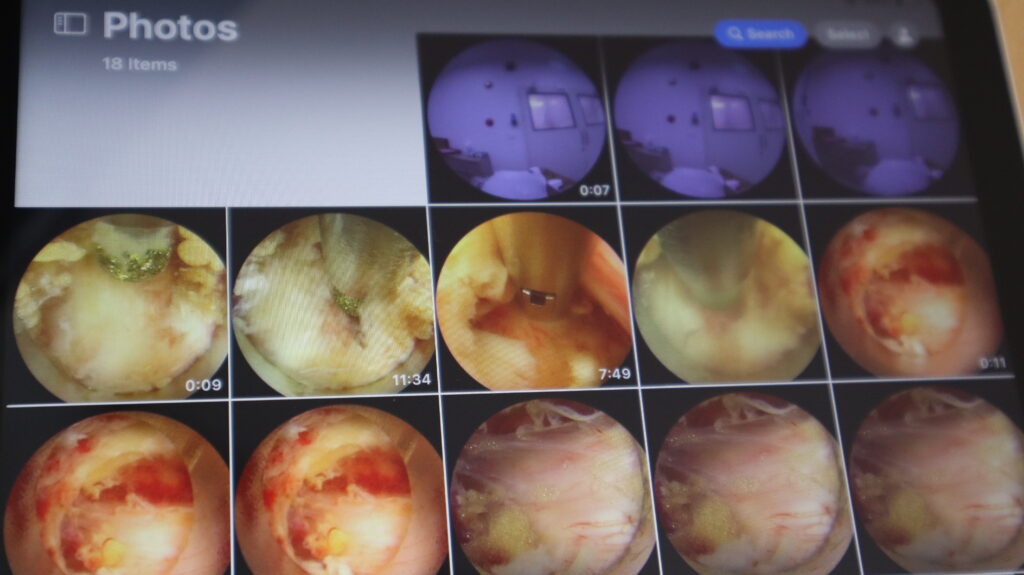

วิทยการการรักษาที่ว่านี้คือ เอนโดสปาย (EndoSpine): ผ่าตัดเฉพาะจุด เห็นชัด ปลอดภัยกว่าเดิม เทคโนโลยี EndoSpine คือการผ่าตัดผ่านกล้องชนิดพิเศษที่ออกแบบมาเฉพาะสำหรับกระดูกสันหลัง ช่วยให้แพทย์สามารถมองเห็นจุดที่กดทับเส้นประสาทได้อย่างชัดเจน และผ่าตัดเฉพาะส่วนที่จำเป็นโดยไม่กระทบต่อโครงสร้างรอบข้าง ข้อดีคือเราแก้ไขเฉพาะจุด ไม่ต้องรื้อโครงสร้างทั้งหมด แผลเล็ก เสียเลือดน้อย ความเสี่ยงต่ำ และฟื้นตัวได้เร็ว”

ปัจจุบัน Endospine Center ศูนย์กระดูกสันหลังและข้อ รพ วัฒนา อุดรธานี ถือเป็นโรงพยาบาลเอกชนแห่งเดียวในภาคอีสาน ที่มีเทคโนโลยีกล้อง EndoSpine รุ่นใหม่ล่าสุด ซึ่งให้ภาพขยายคมชัดระดับมิลลิเมตรช่วยลดโอกาสการบาดเจ็บต่อเส้นประสาทได้อย่างมากนอกจากนี้ การผ่าตัดด้วยเทคนิคนี้ยังสามารถทำได้โดย ฉีดยาชาเฉพาะจุดผู้ป่วยบางรายสามารถ “มาเช้าเย็นกลับ” ได้โดยไม่ต้องดมยาสลบ